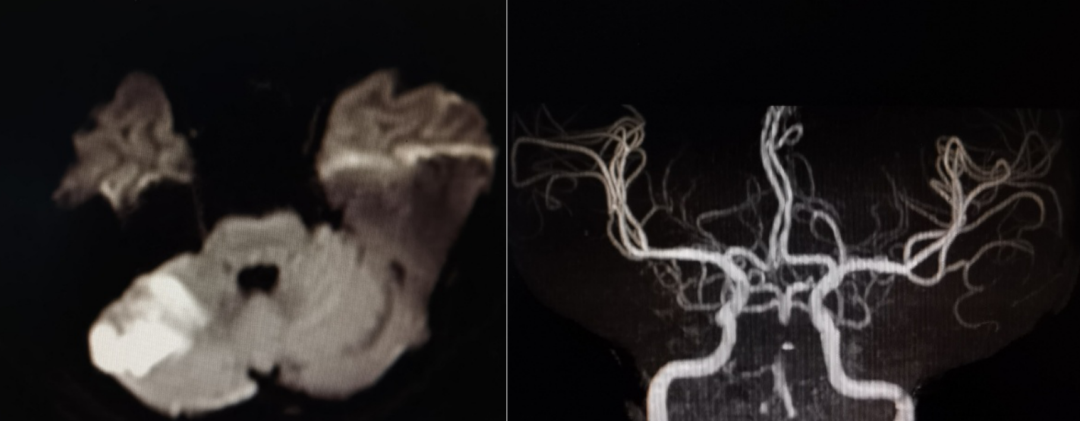

入院颅脑MRI+MRA可见右侧小脑新发梗死,基底动脉中段显影欠佳。

全脑血管造影提示右椎纤细,颅内段不显影。左椎颅内段发出小脑后下动脉已远闭塞,但部分血管吻合,使左椎V4远端浅淡显影。

前循环造影提示后交通开放,基底动脉逆向显影,基底动脉中下段血管床未显影。